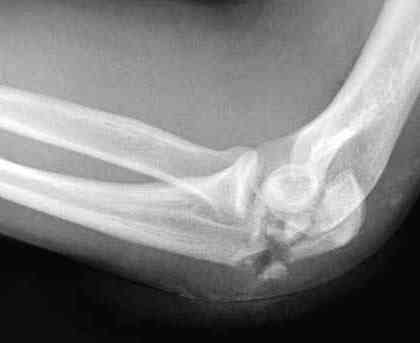

Здесь выставлены несколько случаев и варианты фиксации локтевого отростка, некоторые в комбинации с другими переломами.

перелом локтевого отростка с переломом головки лучевой кости (использованы 2 мм шурупы)

3 вариант

перелом с capitelum humerus и проксимальной трети улна